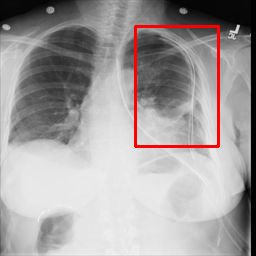

Deployments of artificial intelligence in medical diagnostics mandate not just accuracy and efficacy but also trust, emphasizing the need for explainability in machine decisions. The recent trend in automated medical image diagnostics leans towards the deployment of Transformer-based architectures, credited to their impressive capabilities. Since the self-attention feature of transformers contributes towards identifying crucial regions during the classification process, they enhance the trustability of the methods. However, the complex intricacies of these attention mechanisms may fall short of effectively pinpointing the regions of interest directly influencing AI decisions. Our research endeavors to innovate a unique attention block that underscores the correlation between 'regions' rather than 'pixels'. To address this challenge, we introduce an innovative system grounded in prototype learning, featuring an advanced self-attention mechanism that goes beyond conventional ad-hoc visual explanation techniques by offering comprehensible visual insights. A combined quantitative and qualitative methodological approach was used to demonstrate the effectiveness of the proposed method on the large-scale NIH chest X-ray dataset. Experimental results showed that our proposed method offers a promising direction for explainability, which can lead to the development of more trustable systems, which can facilitate easier and rapid adoption of such technology into routine clinics. The code is available at www.github.com/NUBagcilab/r2r_proto.